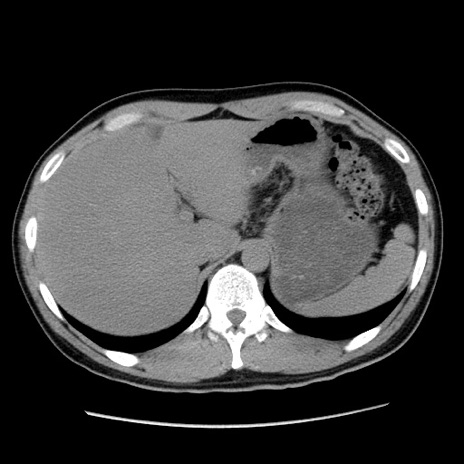

症例36(横断像)

【症例】20歳代 男性

【主訴】心窩部痛

【現病歴】今朝より上腹部痛あり。一旦軽快していたが再度出現したため救急要請。昨日夕に白身の魚を含む刺身を食べた。

【身体所見】BP 136/89mmHg、HR 74/min、BT 37.0℃、腹部:膨満、軟、心窩部に圧痛あり。反跳痛なし、筋性防御なし、腸雑音やや亢進あり。

【データ】WBC 17700、CRP 0.48